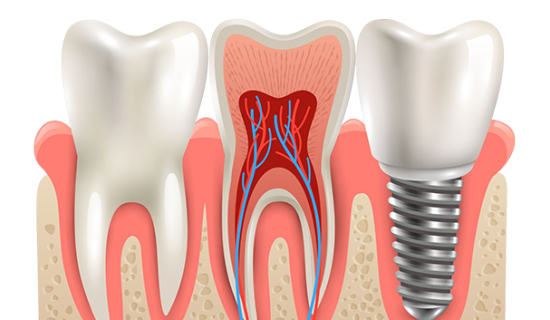

Implantes DentáriosRestaure sua confiança e volte a sorrir sem medo com os melhores implantes dentários disponíveis, feitos sob medida para você. Agende uma consulta |

O procedimento de colocação de implantes dentários pode ser incrivelmente simples e efetivo, sendo altamente recomendado para uma ampla variedade de pacientes. Agende agora sua consulta, vagas limitadas!

A essensity Odontologia oferece quatro tipos de implantes dentários para atender às suas necessidades e proporcionar um sorriso saudável e estético: o implante unitário, o implante duplo, o protocolo e a carga imediata. O implante unitário é indicado para casos em que apenas um dente precisa ser substituído. Já o implante duplo é ideal para casos de falta de dois dentes próximos. O protocolo é uma opção para pacientes que precisam reabilitar toda a arcada dentária, enquanto a carga imediata é indicada para casos em que é possível fixar os dentes no mesmo dia da cirurgia. Nossos profissionais altamente capacitados utilizam as técnicas mais avançadas e equipamentos de última geração para garantir um resultado duradouro e satisfatório. Não deixe de agendar uma consulta e descubra qual tipo de implante é ideal para você. Venha conhecer a essensity Odontologia e transforme o seu sorriso!